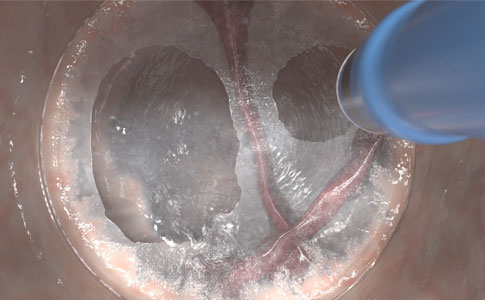

Gezielte Anhebung der Submukosa durch die nadelfreie und gewebeselektive Hydrodissektion, ganz ohne Instrumentenwechsel.

- Gleichmäßigere und zuverlässigere Gewebedissektion und Anhebung der submukösen Gewebeschichten im Vergleich zu herkömmlichen Injektionsnadeln, selbst bei schwierigen anatomischen Verhältnissen wie im Bereich von Falten oder submuköser Fibrose

- Isolation und Freilegung von Gefäßen, Kompression von Blutgefäßen zur Verringerung des Blutungsrisikos